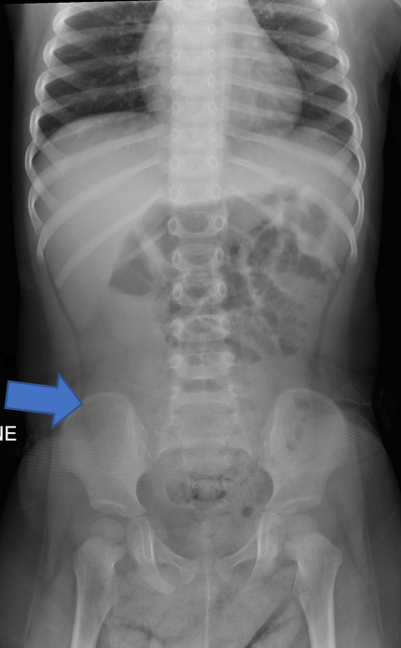

(Figure 3)

Figure 3: Supine and left decubitus abdomen radiographs.

- There is paucity of gas in the ascending colon (arrow).

- The ascending colon is partially air-filled on the left decubitus view, with a soft tissue density in the cecum (arrowhead). This soft tissue density is delineated by air, resembles the crescent sign. No evidence of peritoneal free air.